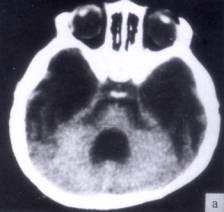

问题 病历摘要:??患者女性,10岁。结核性脑膜炎愈后8月,头痛伴恶心呕吐1周,并渐加重。体检:神清,精神差,反应迟钝,双眼底视神经乳头水肿,双眼外展差,余未见明显异常。 侧脑室-腹腔分流术后并发症包括下列哪些?

选项 A.分流管堵塞 B.分流过度 C.分流不足 D.硬膜下积液 E.感染 F.硬膜下血肿 G.癫痫

答案 ABCDEFG

解析 ABCDEFG